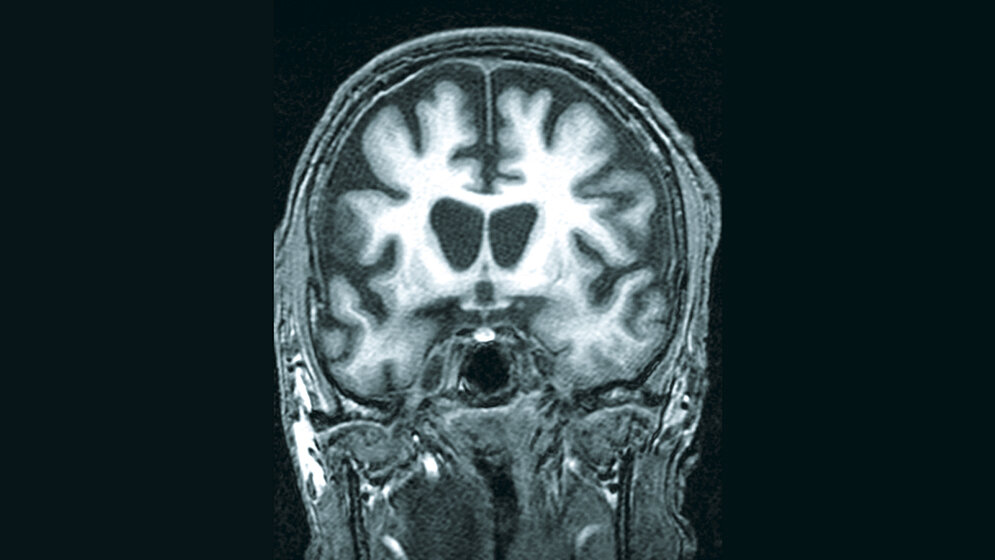

Chorea Huntington ist eine Erbkrankheit, bei der die Nachfahren ein Risiko von 50 % haben zu erkranken. Neben psychischen Veränderungen, die zu Beginn der Erkrankung vorherrschen, treten Bewegungsstörungen auf. Diese Hyperkinesen sind unwillkürliche, plötzliche und unregelmäßige Bewegungen. Sie betreffen die Extremitäten, aber auch die Kau- und Gesichtsmuskulatur. Genetische Ursache ist eine abnorm häufige Wiederholung eines Nukleotid-Tripletts. Pathophysiologisch zeigt sich eine Atrophie bestimmter Hirnregionen. Die Erkrankung verläuft chronisch progredient und kann nicht ursächlich behandelt werden. Es erfolgt lediglich eine Symptomminderung durch Arzneimittel. Die Patienten versterben innerhalb von 15–20 Jahren.